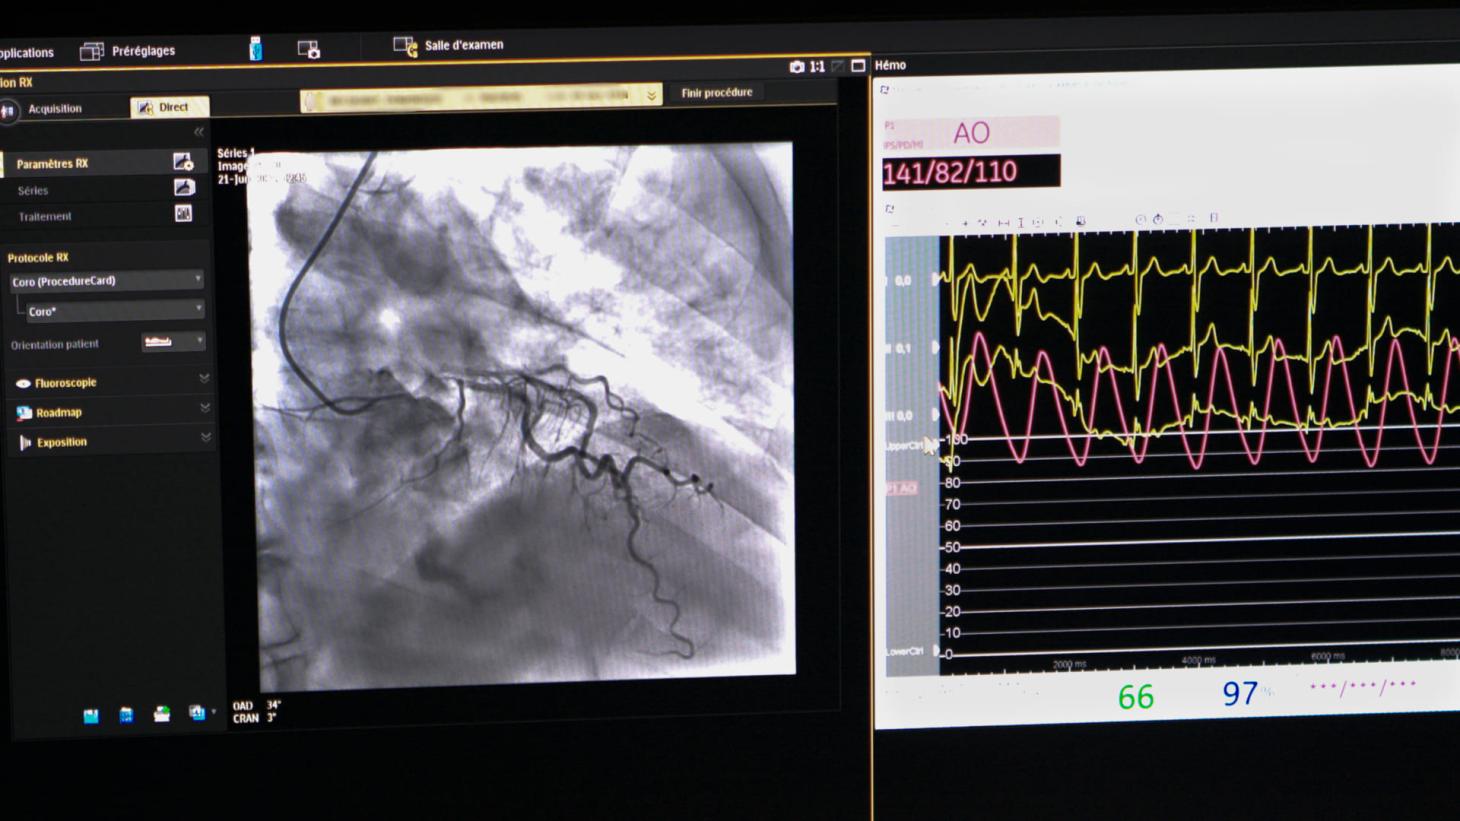

Ces dernières années, l’unité a initié une dynamique forte autour des technologies de santé, en particulier grâce à l’imagerie cardiaque. Ce champ d’innovation est structuré autour de la création du CoreLab CoroTECH, plateforme centralisée permettant de transférer, collecter et analyser des images médicales à l’aide de méthodes d’intelligence artificielle (IA). CoroTECH devient un outil stratégique pour le développement de dispositifs médicaux et de logiciels innovants.

CoroTECH : une plateforme centrale au service de l’innovation

Tous ces projets sont articulés autour de notre CoreLab CoroTECH, qui centralise les données d’imagerie, les valorise pour l’entraînement des algorithmes d’IA et soutient la création de solutions diagnostiques et pronostiques de nouvelle génération. Il s’agit d’un outil clé pour le développement, l’évaluation et la diffusion de technologies de rupture en cardiologie.